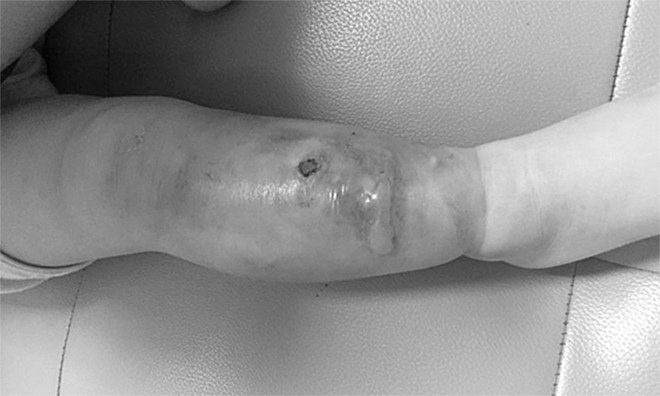

Theo thông tin từ báo Giao thông, mới đây, các bác sĩ Bệnh viện Đa khoa Hùng Vương, Phú Thọ vừa tiếp nhận điều trị cho bé trai 1 tuổi (sống tại Bắc Quang, Hà Giang) đến khám với cẳng chân sưng nề, nóng đỏ, nhiều mụn mủ nhỏ màu vàng kèm theo bé sốt 38 độ 5.

Mẹ bé cho biết, khoảng 4 ngày trước khi vào viện bé bị mọc một nốt mụn nhỏ ở cẳng chân phải, gia đình chủ quan chỉ nghĩ do muỗi đối, ngứa ít ngày là hết.

Tuy nhiên, 2 ngày sau nốt mụn sưng to có mủ trắng, gia đình đắp miếng cao tan vào nốt mụn nhưng tình trạng không đỡ. Thấy con sốt cao, quấy khóc, ăn kém, cẳng chân phải sưng to, nóng đỏ, mọc thêm nhiều nốt mụn mủ, gia đình vội đưa bé đến viện khám.

Qua các kết quả cận lâm sàng bé được các bác sĩ chẩn đoán bị viêm mô tế bào cẳng chân phải và tư vấn gia đình cần phải để bé nhập viện điều trị ngay vì nếu không điều trị sẽ biến chứng rất nguy hiểm.

Chân bé trai sưng phồng, đầy mủ - Ảnh: Bệnh viện Đa khoa Hùng Vương